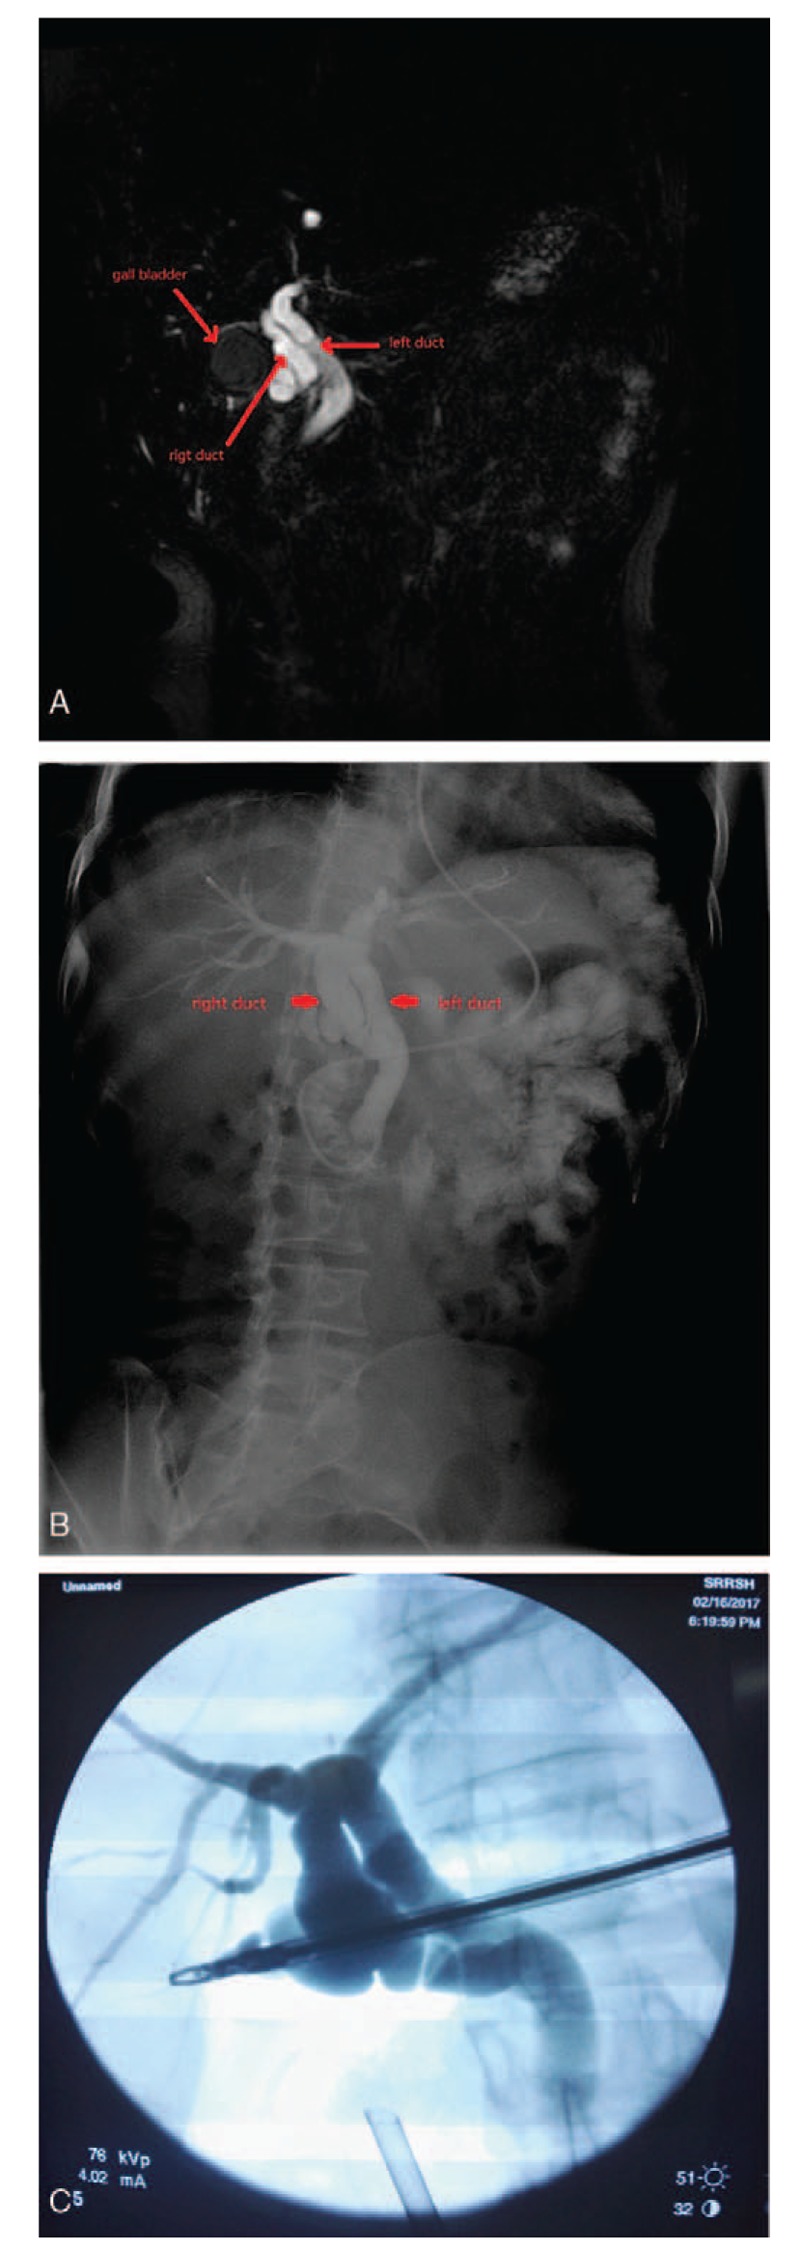

A 44-year-old Chinese woman was admitted to a local hospital April 2017 due to persistent upper abdominal pain and vomiting for 12 days. The ultrasonography of the abdomen performed at the local hospital revealed a swollen gallbladder with the presence of gallstone and cholecystitis. The episodes of pain were not relieved by antibiotic treatment with cefuroxime. The patient then came to Sir Run Run Shaw Hospital for a second opinion and further treatment. At the time of admission, the patient’s physical examination revealed severe tenderness in the upper right quadrant of the abdomen with positive Murphy sign without rebound tenderness or muscle tension. The patient’s liver biochemistry indicated a cholesteric profile, including an alkaline phosphatase of 225 U/L (normal U/L), γ-glutamyl transferase value of 371 U/L (normal U/L), a total bilirubin of 80.5 U/L (normal U/L), and a direct bilirubin of 64.0 U/L (normal U/L). The results of the liver function test were evaluated, including an alanine aminotransferase of 164 U/L and an aspartate aminotransferase of 233 U/L. Serum amylase and lipase indicated an acute pancreatitis (serum amylase 2564 U/L; serum lipase 4495 U/L). Enhanced computed tomography (CT) examination performed at Sir Run Run Shaw Hospital revealed diffuse dilatation of the intrahepatic and extrahepatic bile ducts, with suspected common bile duct obstruction and gallstones. Magnetic resonance cholangiopancreatography (MRCP) also disclosed diffuse dilatation of the intrahepatic and extrahepatic bile ducts, but no obvious filling-defect was found in the CBD lumen (Fig. 1A). The levels of serum amylase and lipase decreased rapidly after conservative treatment, which included enough fluid support and antibiotic. Endoscopic retrograde cholangiopancreatography (ERCP) was subsequently performed and demonstrated the presence of 2 extrahepatic bile ducts with calculus at the distal end of the CBD. On ERCP, it was observed that the extrahepatic bile duct was separated into 2 ducts directly after the confluence of left and right hepatic ducts, and rejoined as a single duct and opened into the duodenum at the normal site (Fig. 1B). Laparoscopic cholecystectomy (LC) was performed after this patient recovered from ERCP. Choledochoscopy during the LC also showed common bile duct duplication, and the cystic duct was seen draining into the right-sided extrahepatic duct (Fig. 1C). This 44-year-old female patient was discharged 2 days after LC. Pathological examination of the resected gallbladder and duct revealed a benign gallbladder with chronic cholecystitis. The patient was doing well after 6 months of follow-up.